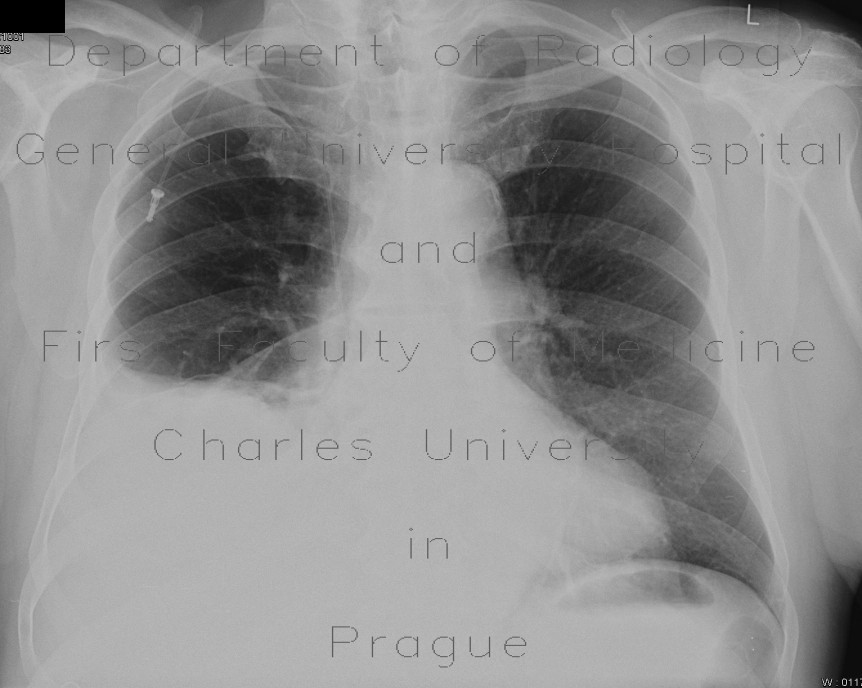

From idiazzaidi.blogspot.com

EDDYCOOL STORY MASSIVE PLEURAL EFFUSION VS LUNG COLLAPSE Can Pleural Effusion Go Away Pleural effusions are diagnosed in about 1.5 million individuals in the united states annually [1]. Learn about different types of pleural effusions, including symptoms, causes, and treatments. A pleural effusion results when fluid collects between the parietal and visceral pleural surfaces of the thorax. The outlook or prognosis varies depending on what caused your pleural effusion and what other conditions. Can Pleural Effusion Go Away.